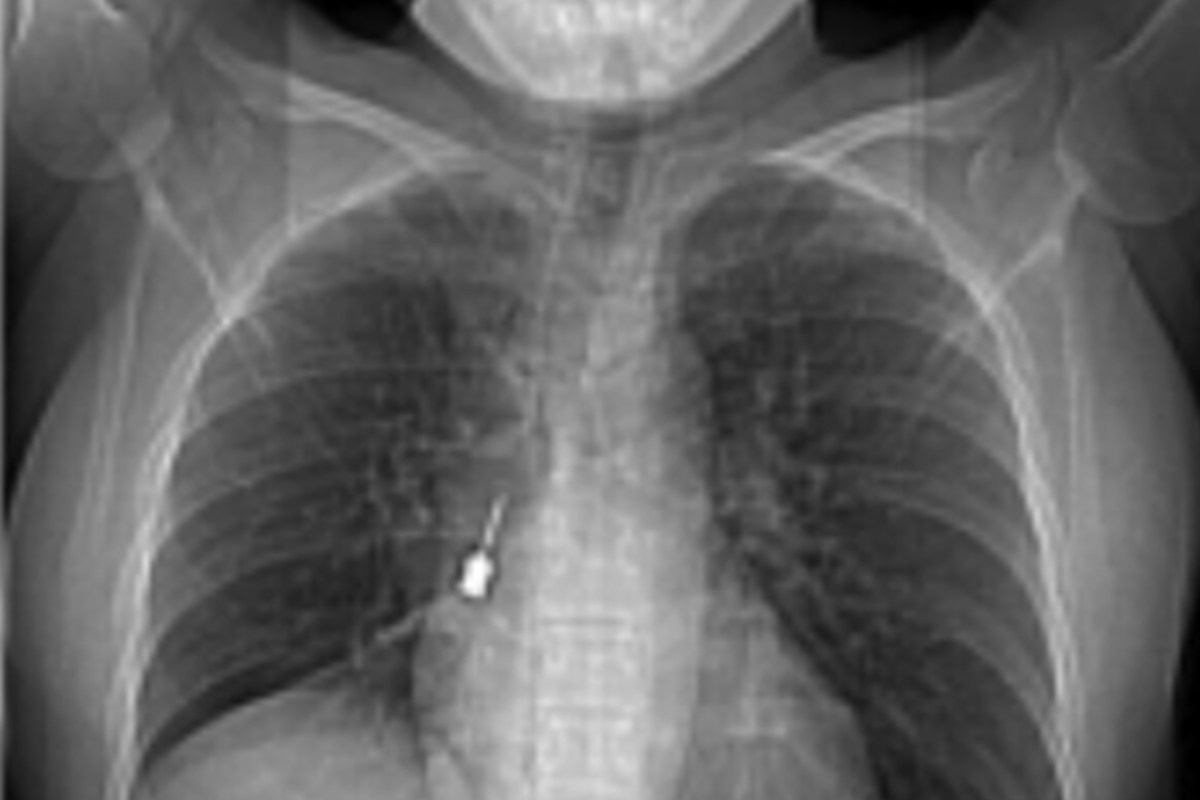

L’esame diagnostico ha rivelato una scoperta tanto sorprendente quanto preoccupante: nel bronco lobare inferiore del polmone destro era rimasto incastrato un cacciavite odontoiatrico, uno strumento utilizzato durante interventi di implantologia dentale. L’oggetto metallico sarebbe stato inalato accidentalmente alcuni giorni prima, senza che la paziente si rendesse immediatamente conto della gravità dell’accaduto.

Gli esami clinici hanno evidenziato non solo la presenza del corpo estraneo, ma anche aria nello spazio tra i due polmoni, una condizione che poteva comportare serie complicazioni. Per questo motivo la donna si è rivolta con urgenza al pronto soccorso, dove è stata immediatamente ricoverata. I medici hanno disposto un intervento chirurgico urgente di estrazione broncoscopica.

Il decorso post operatorio è stato seguito dall’équipe della terapia intensiva post operatoria, coordinata dal dottor Massimo Caracciolo, ed è risultato regolare. La paziente ha risposto bene alle cure ed è stata dimessa in ottime condizioni di salute. Il Grande Ospedale Metropolitano di Reggio Calabria ha confermato l’esito positivo dell’intervento attraverso una nota ufficiale, diffondendo anche le immagini del cacciavite rimosso.